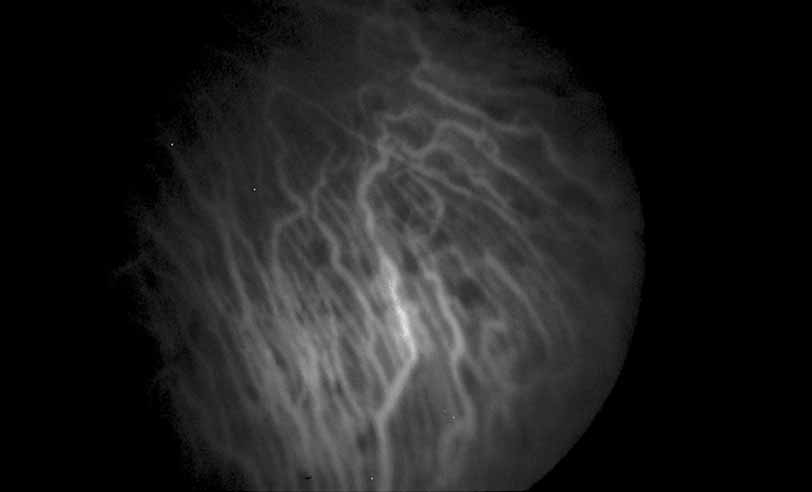

Fig. 1 Serpiginous choroiditis. Early frame of the fluorescein angiogram shows hypofluorescent and hyperflourescent patches extending outward from the optic nerve in a serpiginous pattern (Courtesy of Joseph Michaelson).

Fig. 2 Serpiginous choroiditis. Late frame of the fluorescein angiogram shows extensive staining of previously hypofluorescent zones, with continued hypofluorescence, characteristic of the acute phases of serpiginous choroiditis (Courtesy of Joseph Michaelson).